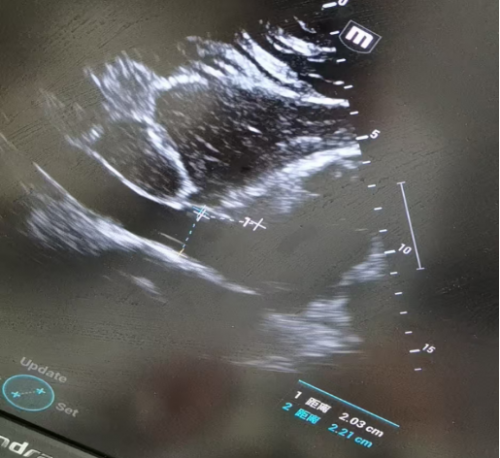

肺部超声:

上蓝点可见A线,双下肺均见B线

IVC(下腔静脉)宽度:2.21cm,变异度差